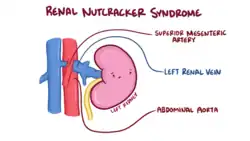

| The nutcracker syndrome results from compression of the left renal vein between the aorta and the superior mesenteric artery. | |

The nutcracker syndrome (NCS) results most commonly from the compression of the left renal vein (LRV) between the abdominal aorta (AA) and superior mesenteric artery (SMA), although other variants exist.[1][2] The name derives from the fact that, in the sagittal plane and/or transverse plane, the SMA and AA (with some imagination) appear to be a nutcracker crushing a nut (the renal vein).